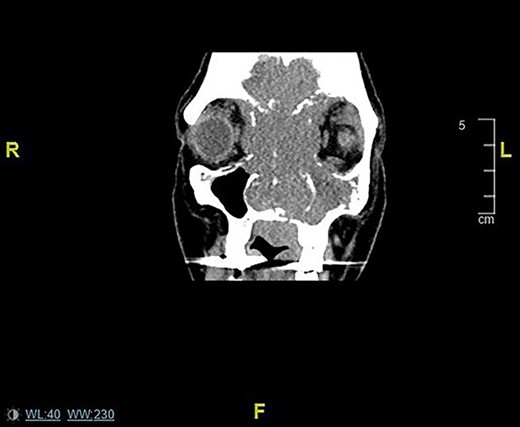

Initially she was assessed by the ophthalmology team and seen to have congestion of the right eye associated with nasal obstruction and left maxillary swelling. When subsequently seen by ENT she was referred for urgent computed tomography (CT) sinuses and review in the head and neck cancer clinic. CT sinuses performed displayed a large malignant mass in the nasal cavity extending to the paranasal sinuses and invading the facial skeleton and anterior skull base (Fig. 1).

Coronal CT sinuses/head images displaying sinonasal mass invading anterior skull base, orbits and intracranially.